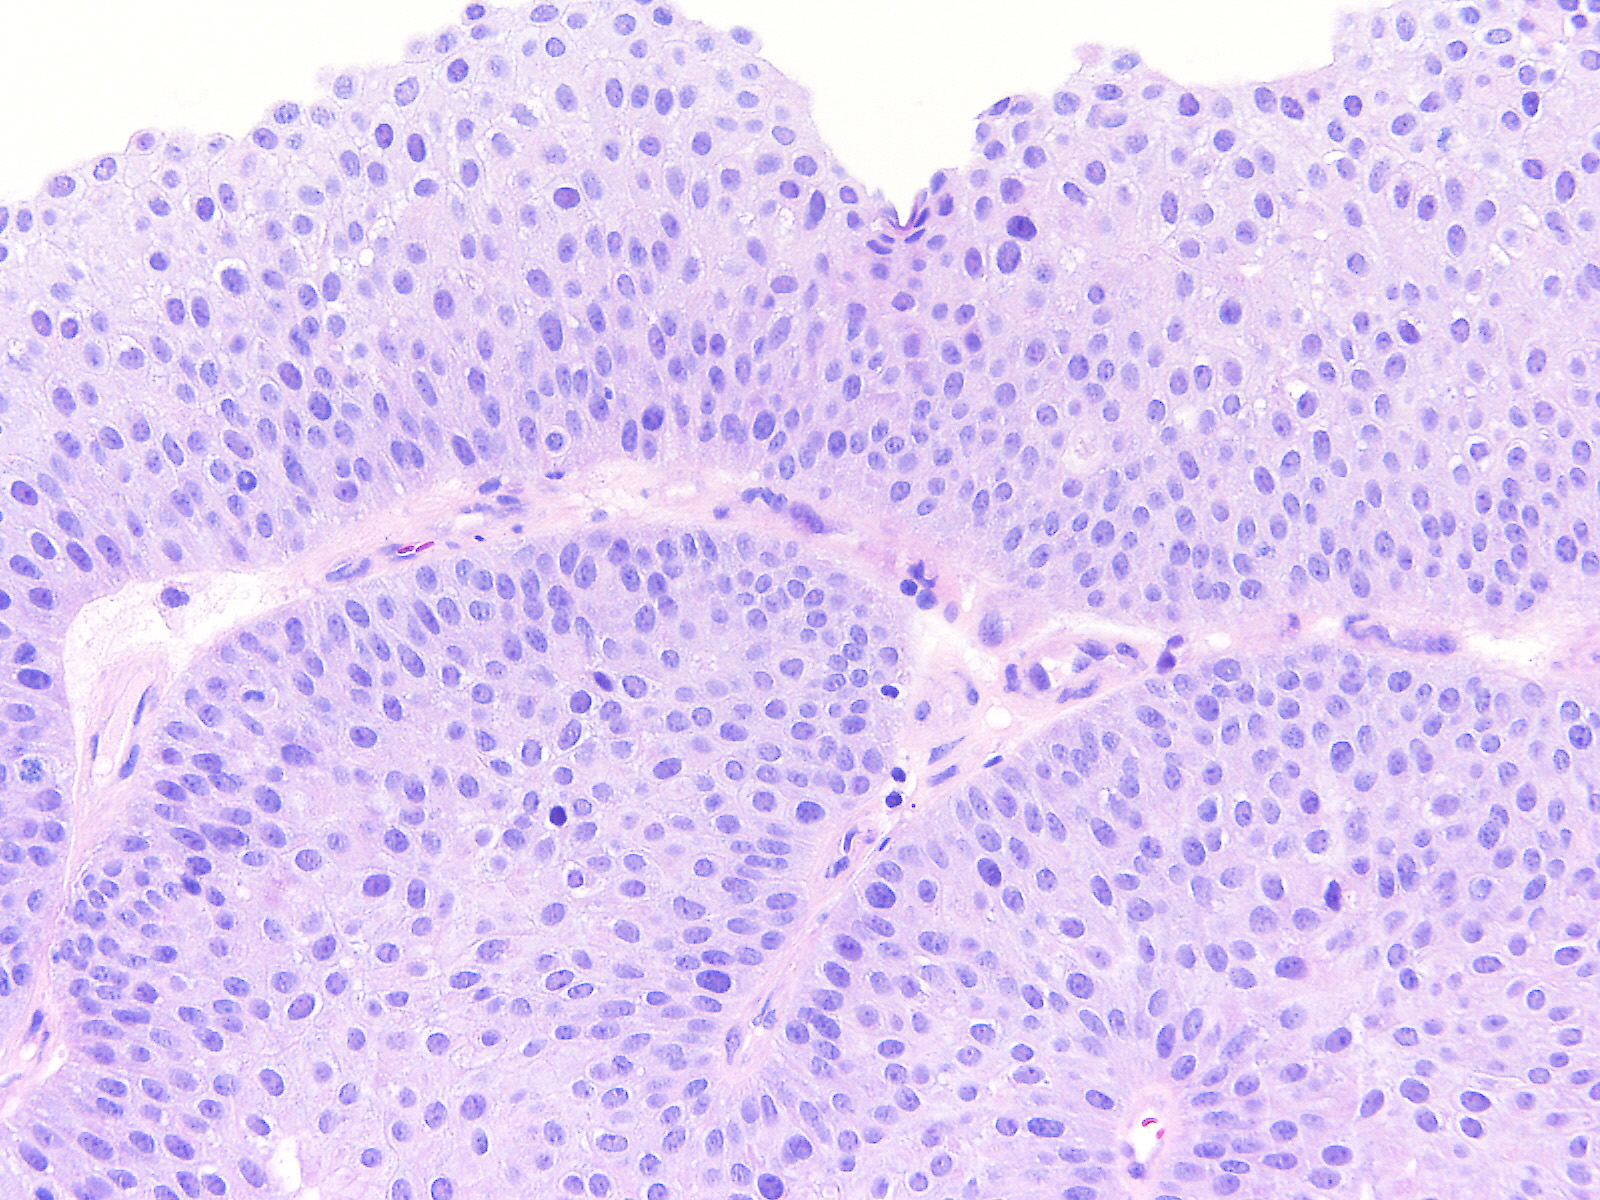

Bladder Papillary Lesions

Case ID: 526